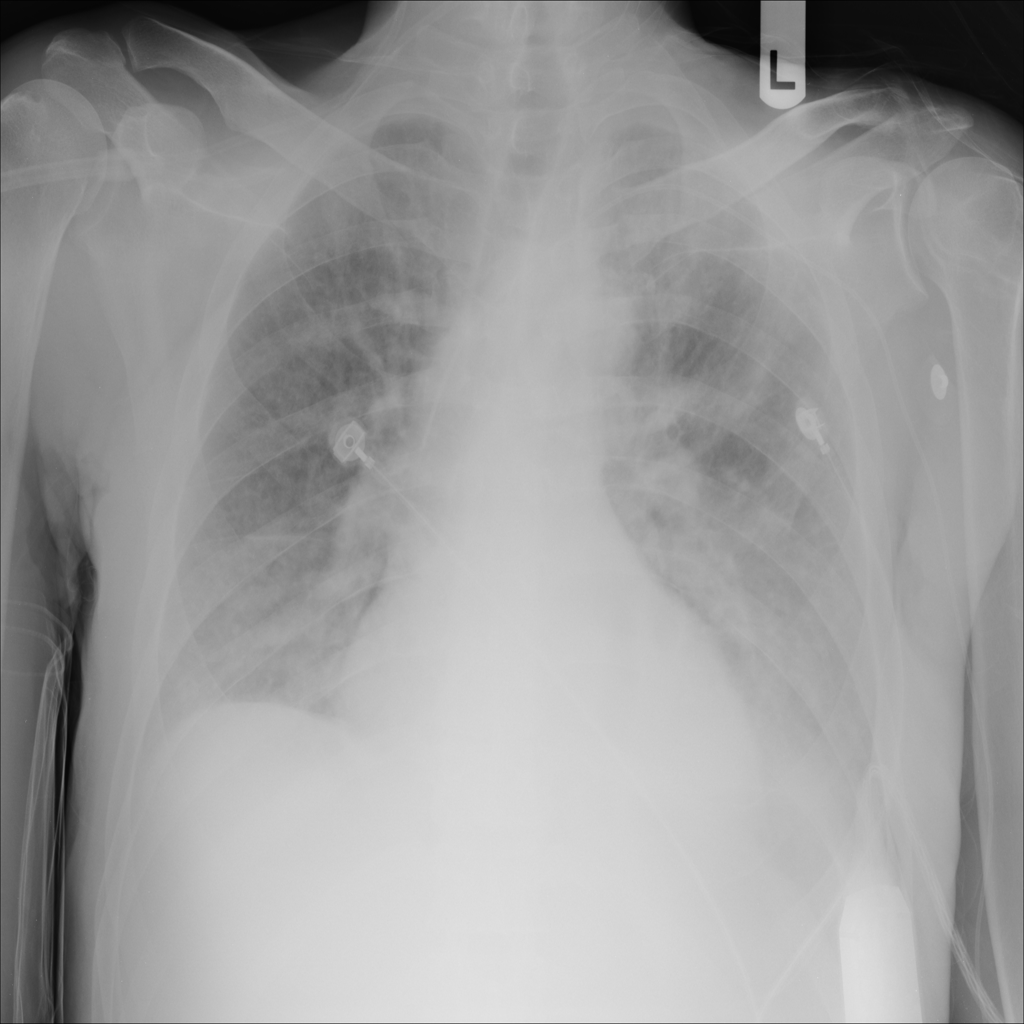

PAT-E828 · IMG-005Edema

PAT-E828 · IMG-005

AP